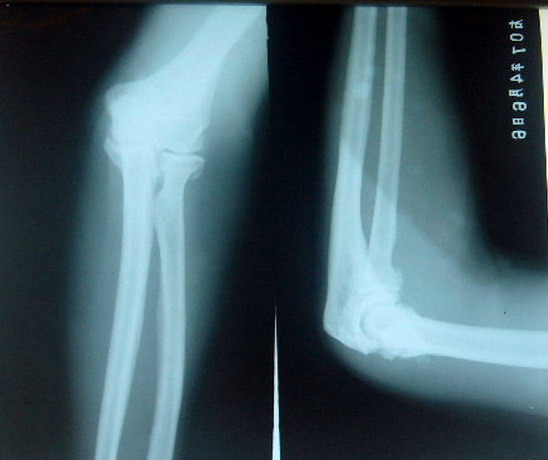

男性70岁。肘部跌伤2天。pe:肘关节肿胀,压痛(+)活动障碍。追问病史患者自诉以往关节稍肿胀,变形.

肘关节各关节面增生硬化,关节腔狭窄,考虑:1增生性关节炎。2创伤性关节炎。

肘关节骨关节炎,未见新鲜骨折

患者男.70岁.外伤2天,未见明显骨折时间短不考虑创伤性关节炎。考虑增生性关节炎.

上图片可能使用的是感兰片,需更换感绿片效果更好,图片清晰,信息量也多。收费可提高,对病人,对医院,对放射科医生都是有好处的。上图病例考虑肘关节骨关节病,桡骨小头是否有新鲜骨折,还需复查。